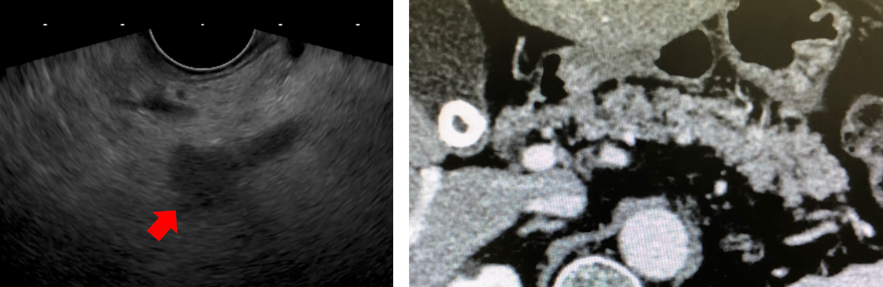

造影CT検査で腫瘍は指摘されなかったが、超音波内視鏡検査では8mm大の低エコー腫瘤を認めた。EUS-FNAの結果、膵管癌 stageⅠAの診断となり手術を行なった。